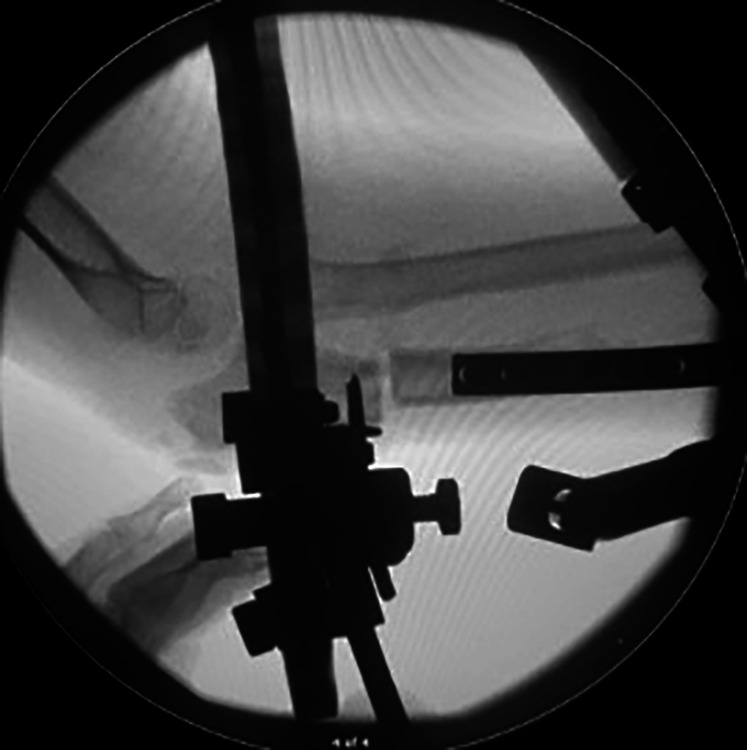

Introduction: Acquired chronic radial head (RH) dislocations present a significant surgical challenge. Coexisting deformity, length discrepancy, and RH dysplasia, in multiply-operated patients often preclude acute correction. This study reports the clinical and radiological outcomes in children, treated with hexapod frames for gradual RH reduction.

Materials and methods: Patient cohort from a prospective database was reviewed to identity all hexapod frames for RH dislocations between 2000 and 2021. Patient demographics, clinical range, and radiographic parameters were recorded.

Results: From a cohort of 127 upper limb frames, 34 chronic RH dislocations (15 anterior and 17 posterior) were identified. Mean age at surgery was 10 years (5-17 years). Six pathologies were reported (17 post-traumatic, 11 multiple hereditary exostosis (MHE), two nail-patella syndrome, two Ollier's disease, one osteogenesis imperfecta, and one rickets). About 76% had a congruent RH reduction at final follow-up. Two MHE cases gradually re-dislocated. Five children had some mild persistent incongruency. Mean follow-up duration was 4.2 years (9 months to 11.5 years). Mean radiographic correction achieved in coronal plane 9°, sagittal plane 7°, and carrying angle 12°. Mean ulnar length gained was 7 mm, and final ulnar variance was 7 mm negative (congenital). All cases achieved bony union, with two requiring secondary bone grafting. Mean frame duration was 166 days. Mean final range of motion was 64° supination, 54° pronation, and 2°-138° flexion.

Conclusion: The majority of children having frame correction achieve complete correction or minor subluxation, which is well tolerated clinically. Frame-assisted reduction is an effective tool for selective complex cases, irrespective of the pathology driving the RH dislocation.